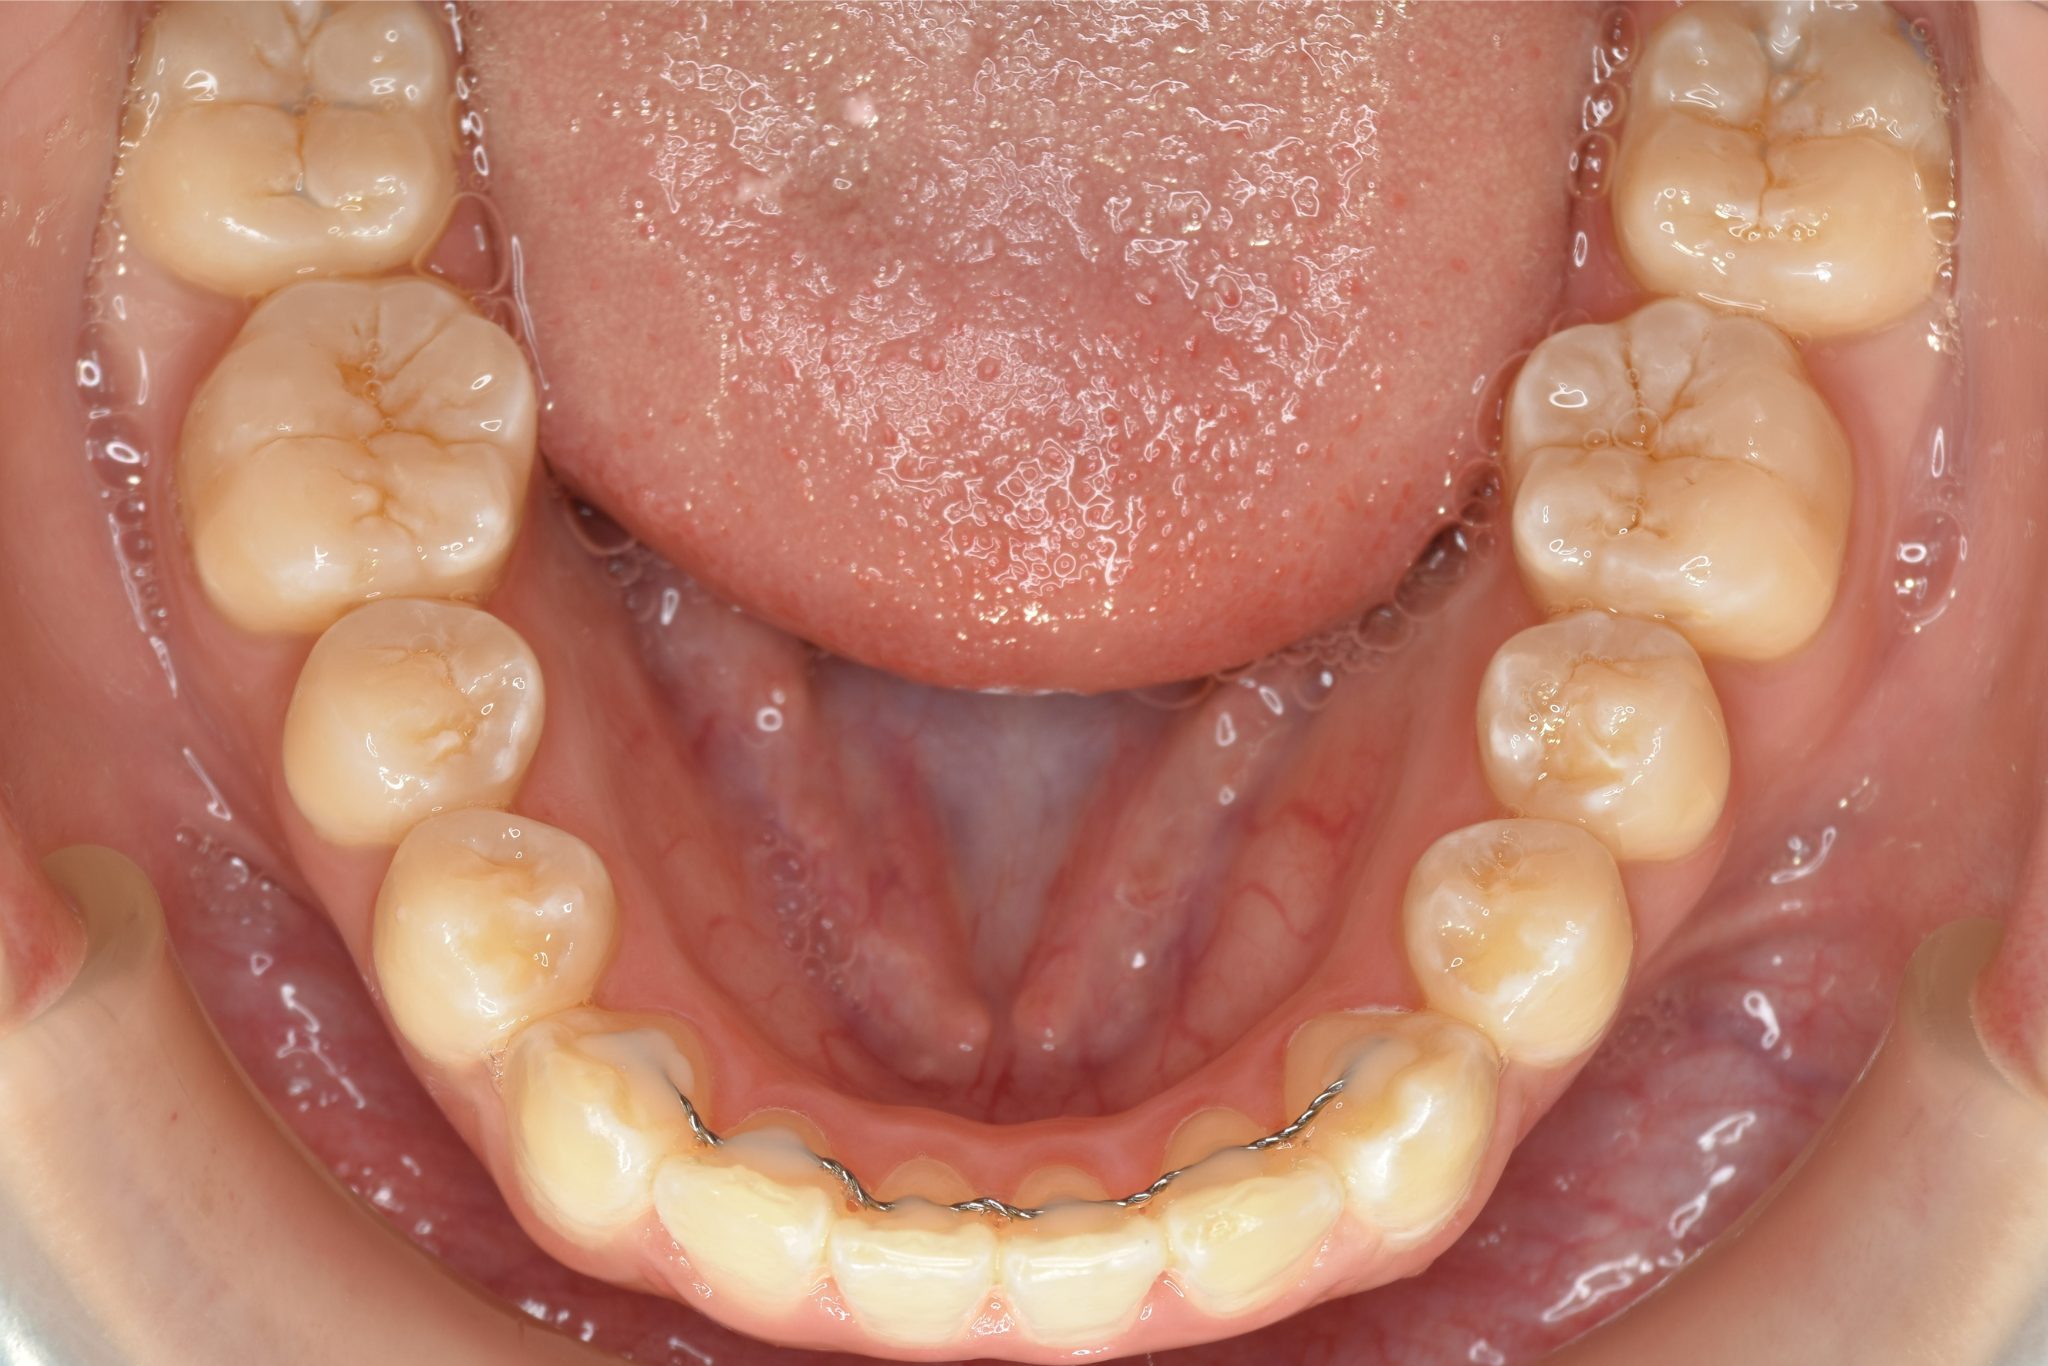

アフター

全顎ワイヤー矯正 症例_815

主訴 前歯の出っ歯|八重歯|下の歯のデコボコ|検診で噛み合わせが悪いと指摘されたこと

施術内容 成人矯正1期治療

治癒期間 1年4か月間

費用 954,800円(税込)